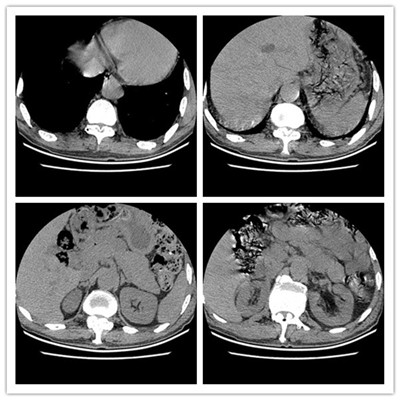

患者张某,男,69余,患者以“腰痛伴双下肢抽痛5年,摔伤后加重伴行走困难6天”在当地诊断为腰椎滑脱伴椎管狭窄(图1),转入我科拟行手术治疗,入院后完善检查,发现患者有广泛严重的胸椎黄韧带骨化伴不全瘫(图2),钙化范围涉及了胸2至腰2节段,且很多节段压迫极其严重(图3),原本相当于大拇指粗细的椎管,被钙化的黄韧带硬生生挤成了一条缝。

图3

该患者,压迫范围如此广泛,且压缩程度如此严重,实属罕见。且患者在查体时发现双下肢肌力3级左右,双侧肌张力明显升高,踝阵挛阳性,患者活动时双下肢有难以自控的抽动,无法自行下地行走。